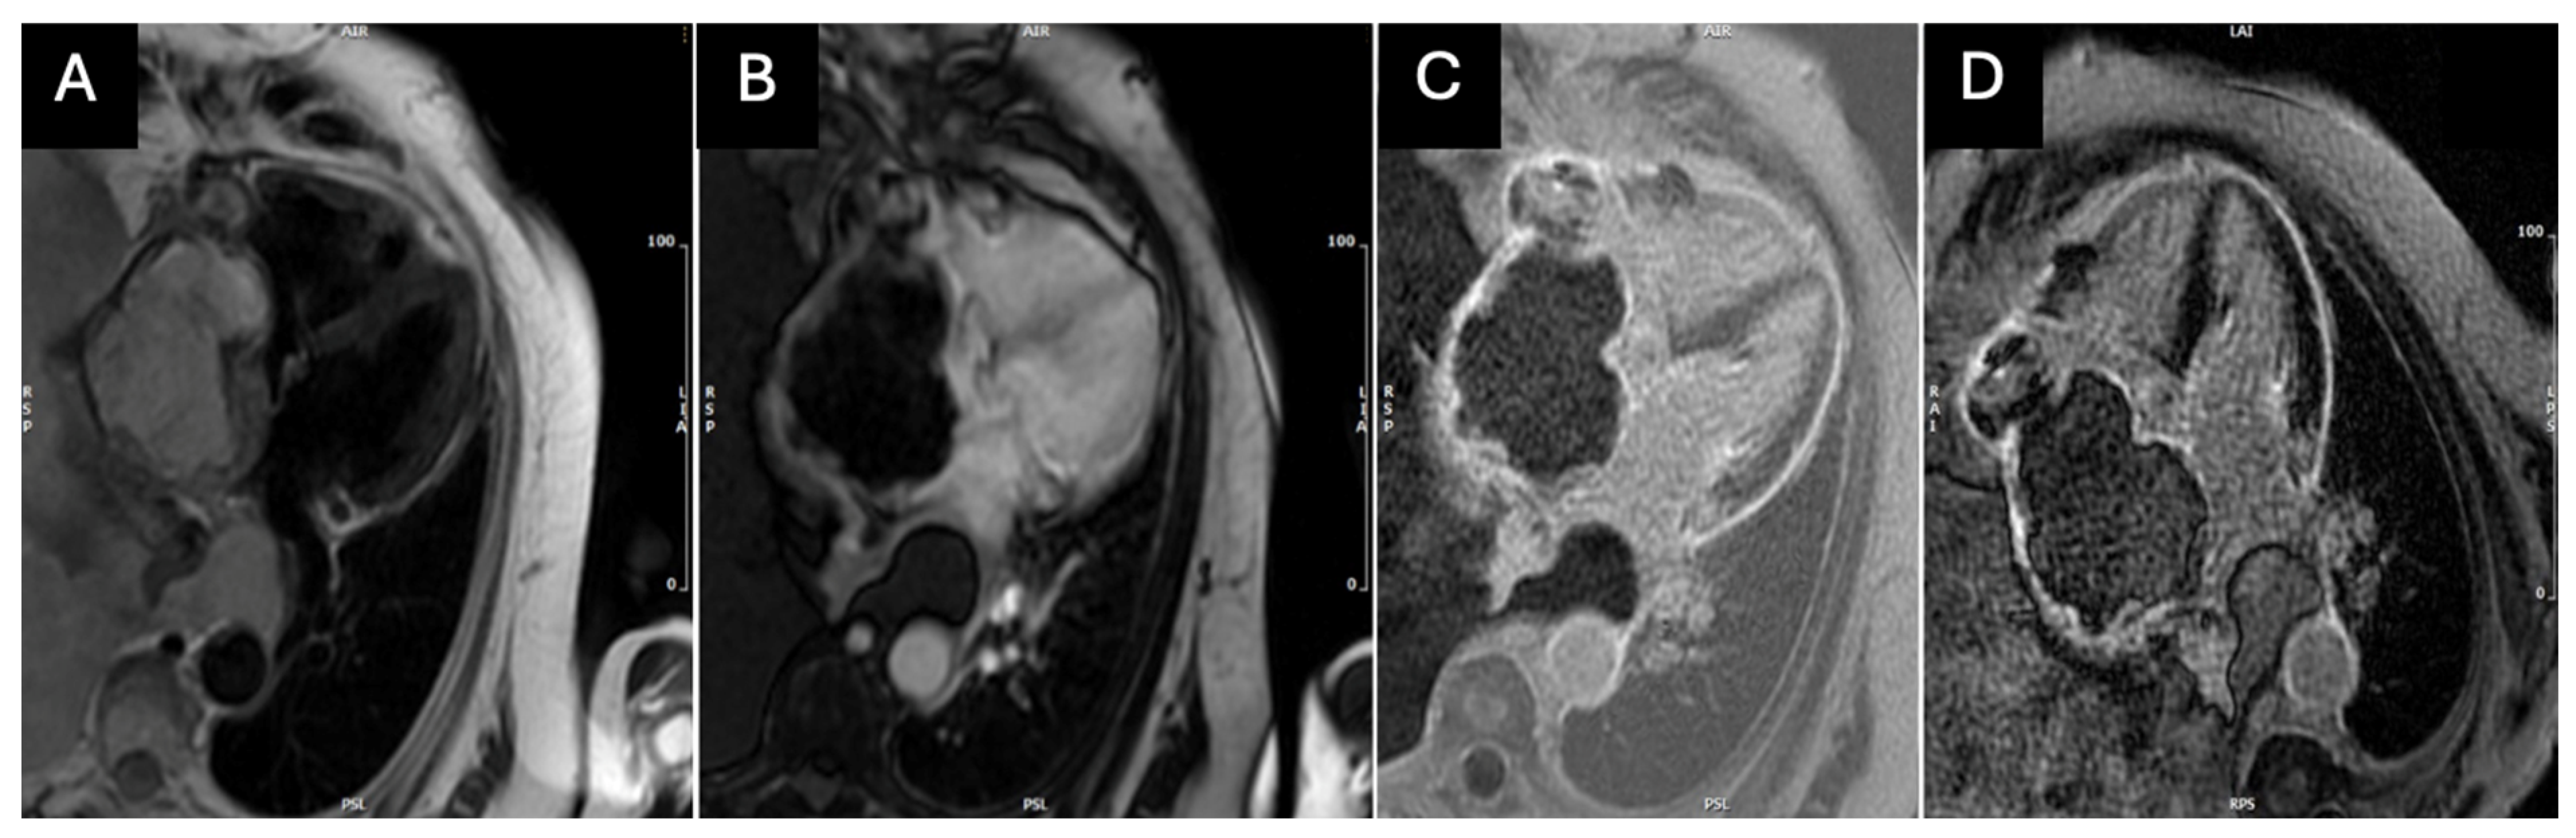

2. Case Presentation

3. Discussion